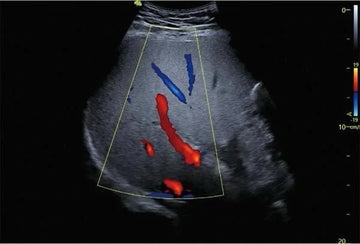

- En la imagen proporcionada, se observa un estudio de una vena (indicado en la parte superior derecha de la pantalla con el término “vena inf.”) en el cual se ha utilizado un Doppler en color para analizar el flujo sanguíneo. Los colores rojo y azul que aparecen en la imagen representan la dirección y la velocidad del flujo sanguíneo en el vaso estudiado:

- Colores rojos y amarillos: Indican el flujo sanguíneo hacia el transductor.

- Colores azules: Indican el flujo alejándose del transductor.